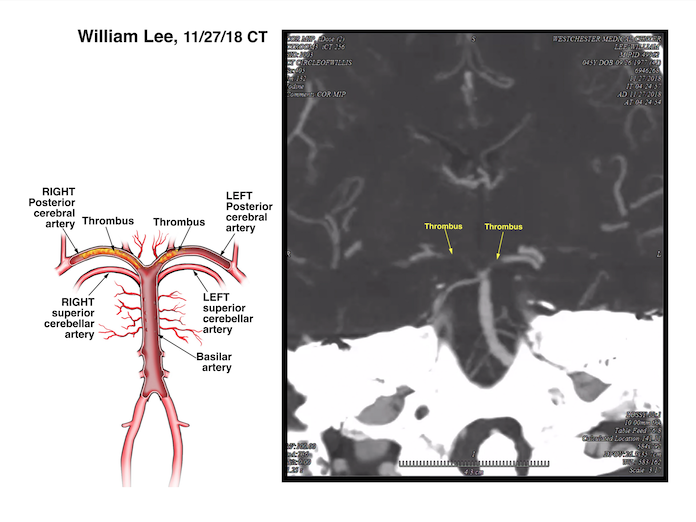

Unfortunately there was no attending physician in the hospital at this time (in the middle of the night). The only doctors on-call at this time were a first year neurology resident and a second year radiology resident. Both of these resident physicians improperly read the CAT scan and failed to note a severe blockage in one of the major arteries in the patient’s brain.

It wasn’t until 3 hours later that an attending neuroradiologist arrived and reviewed the CAT scan. Upon review, this neuroradiologist immediately diagnosed the blockage (a basilar artery occlusion) and directed that the patient be brought in for a procedure to remove the clot. This procedure, known as a thrombectomy, only took 10 minutes to remove the clot. The illustrations above, which were created for use at trial show normal brain anatomy, the offending clot and procedure that was necessary to remove the clot.